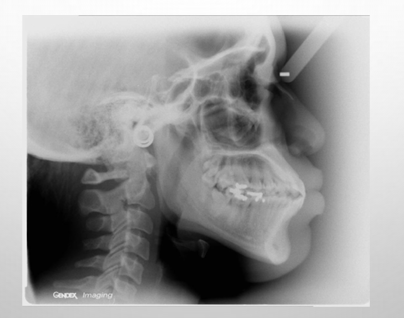

lateral ceph analysis- radiographic analysis

-allows us to see how much of the skeleton is involved in the malocclusion

lateral ceph

-used to determine skeletal positions of maxilla and mandible in relation to each other and the cranial base

-used to determine dentoalveolar positions

-used to determine vertical dimensions of maxilla and mandible